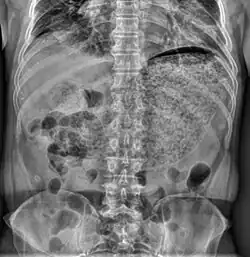

| Simple abdominal X-ray shows gastric distension with a large amount of material in the stomach, suggesting severe gastric hypomotility | |